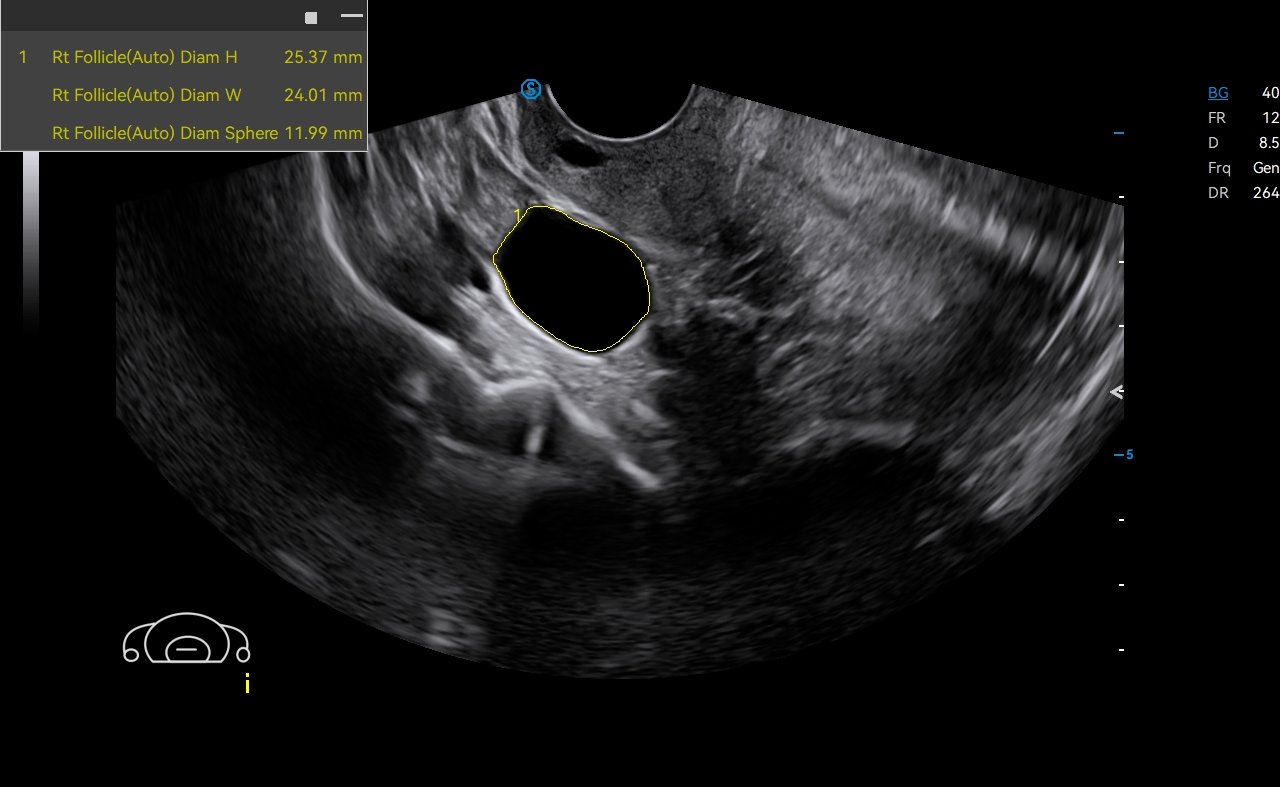

Auto OB automatically measures the common fetal biometric results (HC, BPD, FL, etc.) in standard sections.